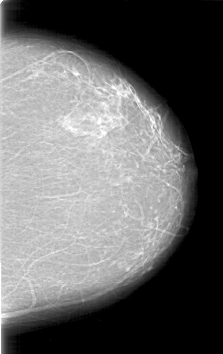

D_4196_1.LEFT_MLO

D_4196_1.LEFT_CC

LEFT_MLO LINES 6841 PIXELS_PER_LINE 4366 BITS_PER_PIXEL 12 RESOLUTION 43.5 NON_OVERLAY

LEFT_CC LINES 6361 PIXELS_PER_LINE 4006 BITS_PER_PIXEL 12 RESOLUTION 43.5 NON_OVERLAY